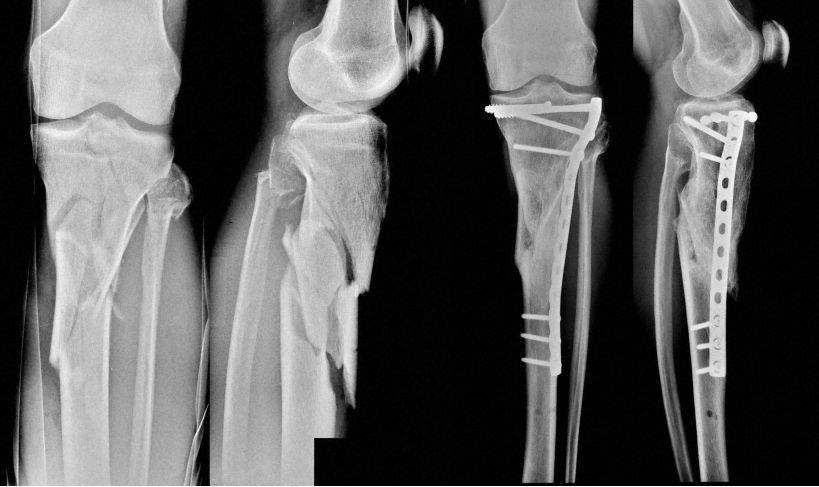

两处腓骨钢板多余(因为下胫腓骨联合没有损伤,特别注意不要犯这种错误)(髓内钉加阻挡钉首选,其次内侧长钢板,如果没有钢板用外固定架也可以)

胫骨远端简单骨折选用钢板固定没有实现坚强固定,钢板承受应力,孔处应力集中断裂

更换长钢板后愈合

下一例:是胫骨骨折局部钢丝螺钉内固定太多干扰骨愈合,骨不连接钢板迟早断裂。

开放骨折,软组织损伤严重,骨不连接导致钢板断裂。应当在伤口愈合后及时干预植骨